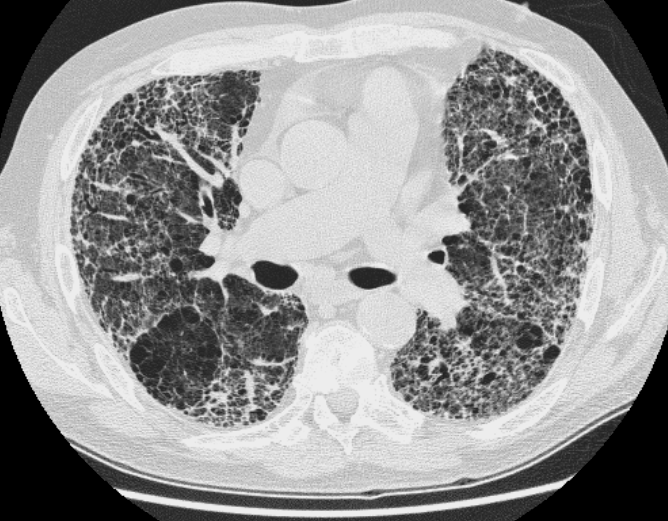

Hrct Chest X Ray Near Me . ideally, an expiratory hrct scan should be performed in all obstructive airway diseases. hrct provides superior evaluation of lung abnormalities. Subpleural honeycombing (red arrow), traction. in most cases, physicians who manage patients with dild will request a.

Subpleural honeycombing (red arrow), traction. hrct provides superior evaluation of lung abnormalities. in most cases, physicians who manage patients with dild will request a. ideally, an expiratory hrct scan should be performed in all obstructive airway diseases.

Hrct Chest X Ray Near Me ideally, an expiratory hrct scan should be performed in all obstructive airway diseases. in most cases, physicians who manage patients with dild will request a. Subpleural honeycombing (red arrow), traction. ideally, an expiratory hrct scan should be performed in all obstructive airway diseases. hrct provides superior evaluation of lung abnormalities.